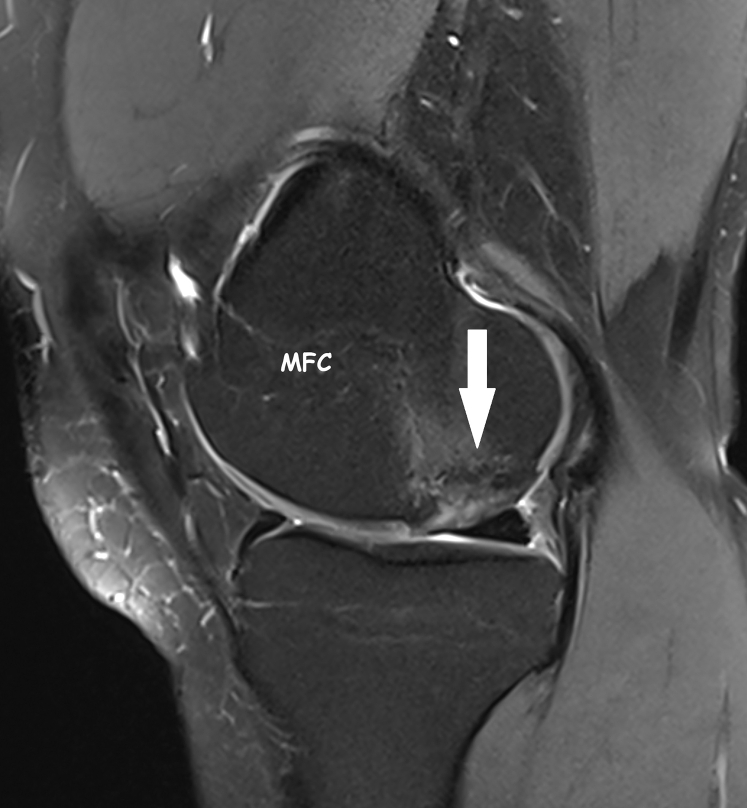

The first stage includes patient’s qualification for the procedure. Planning osteochondral defect reconstruction surgery should include thorough assessment of the location, extent, and depth of the lesion; the mechanical axis of the limb, and the presence of any concomitant lesions [Fig 1]. Based on magnetic resonance imaging (MRI) and orthopaedic surgeon experience, as well as the availability of materials, the optimal surgical approach and the use of additional techniques, materials, or transplants may be determined.3 A thorough interview should be conducted with the patient to exclude bone marrow diseases, with a particular focus on hematological conditions. A standard morphology test with blood smear is performed. In the absence of deviations, the procedure of stimulation of the patient can be started. As a standard, 4 days before surgery, granulocyte colony-stimulating factor (G-CSF) at a dose of 480 μg/d is administered subcutaneously (Zarzio; Sandoz, Vienna, Austria). The patient is monitored for leukocytosis and possible side effects. During this period, mesenchymal stem cells multiply in the bone marrow and are gradually excreted into the peripheral blood. The increase in leukocytosis indicates the effectiveness of stimulation, and its size is usually individually variable.

Fig 1.

Osteochondral lesion (arrow) of the medial femoral condyle (MFC) on sagittal MRI scan of the right knee.